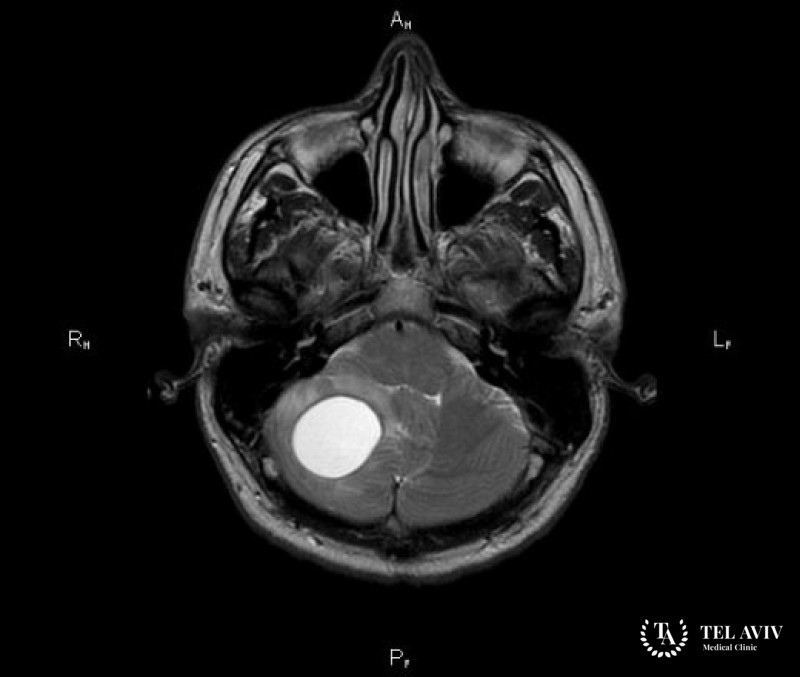

Зачастую диагностика гемангиобластомы затруднена из-за неспецифических симптомов. После тщательного неврологического осмотра и опроса пациента врач может назначить дополнительные офтальмологические исследования, во время которых могут быть выявлены застойные явления на диске зрительных нервов. Также обязательно проводится МРТ, позволяющее определить размеры опухоли и точное место ее локализации.